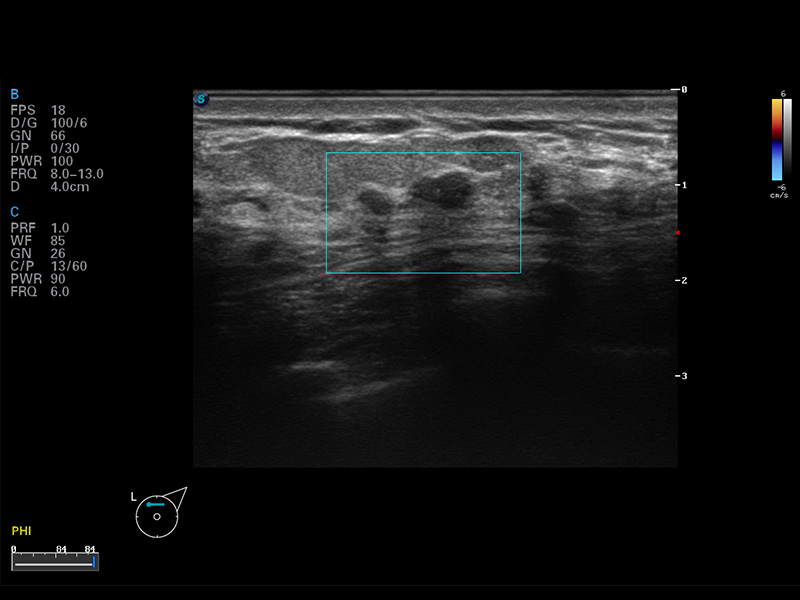

S8 EXP便携式彩色多普勒超声诊断仪是百老汇电子游戏官网研发的高端全身应用型便携彩超。高通道的VIS平台融合可视化(Visual)、智能化(Intelligent)和人性化(Smart)的特点,配以百老汇电子游戏官网自主研发生产的探头大家族,使您能够快速、准确的获得病人信息,提高工作效率的同时减轻疲劳。

成像技术

多波束形成器

μ-Scan微米成像

谐波成像

空间复合成像